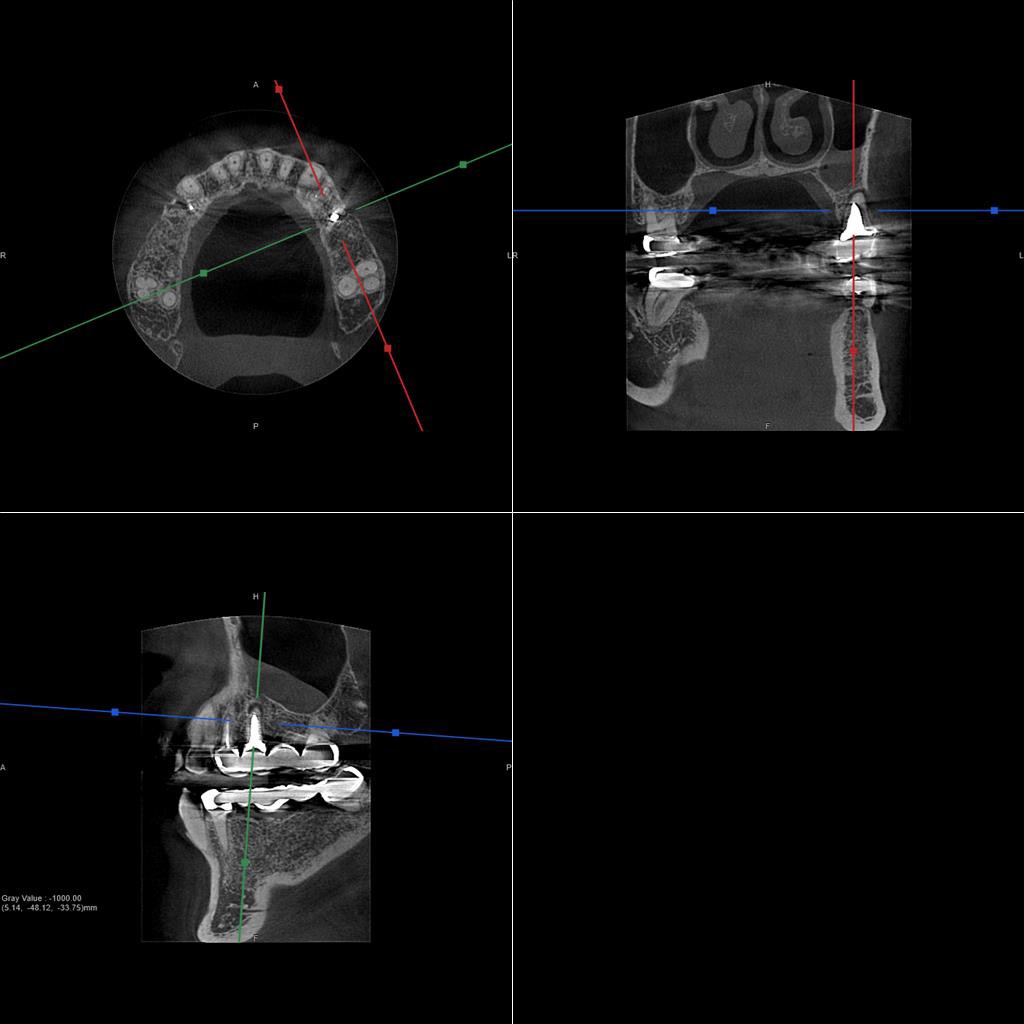

50代、男性、左上に違和感があることを主訴に来院され、インプラント治療を行いました。

| 診断結果 | 左上5番歯根破折 |

| 治療内容 | 抜歯即時インプラント |